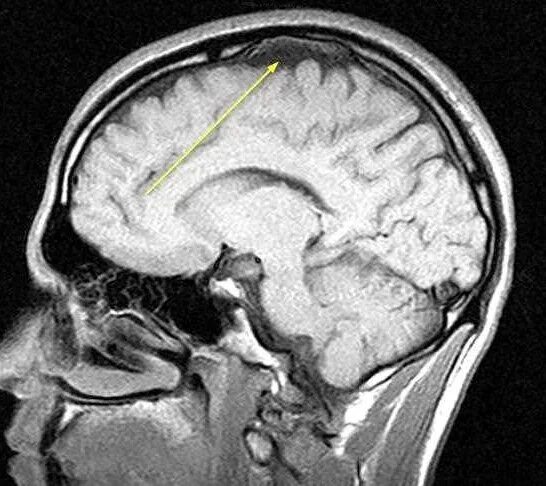

Расширение субарахноидального пространства головного